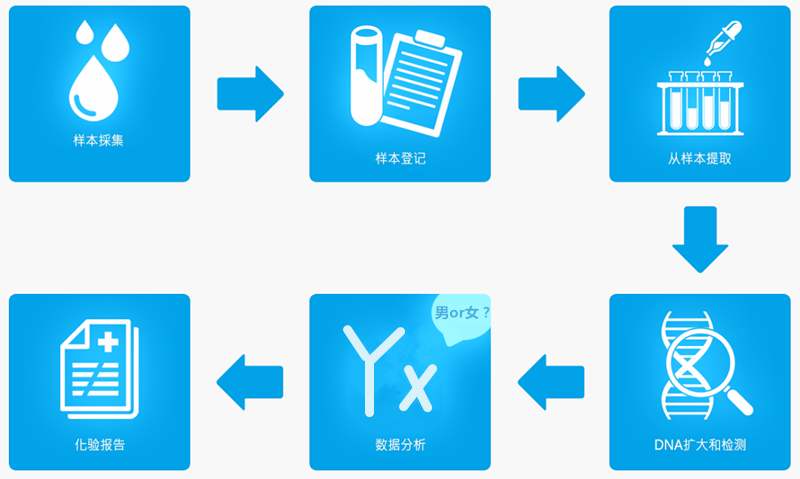

香港验血测男女流程准不准_DNA鉴定该如何预约!

大家如果只要看过关于香港验血验男女的条件检测技术,都是知道香港验血测性别是有几个条件的,不然达不到相应的准确率,其中一项就是在